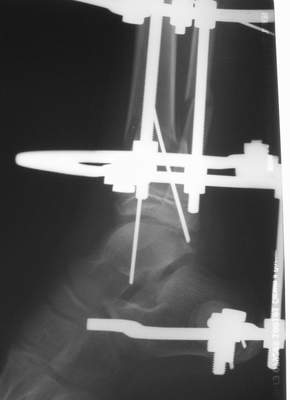

Вытяжение

Фиксация

в гипсе

А аппаратами пользуетесь?

1) з/репозиция, 2) фиксация 2 спицами, 3) аппарат, 4) фиксационные

спицы удалены...

См. аттачт.

А можно было наложить аппарат и по поводу ложного сустава...

По крайней мере не было бы укорочения (пусть и в 2 см)...